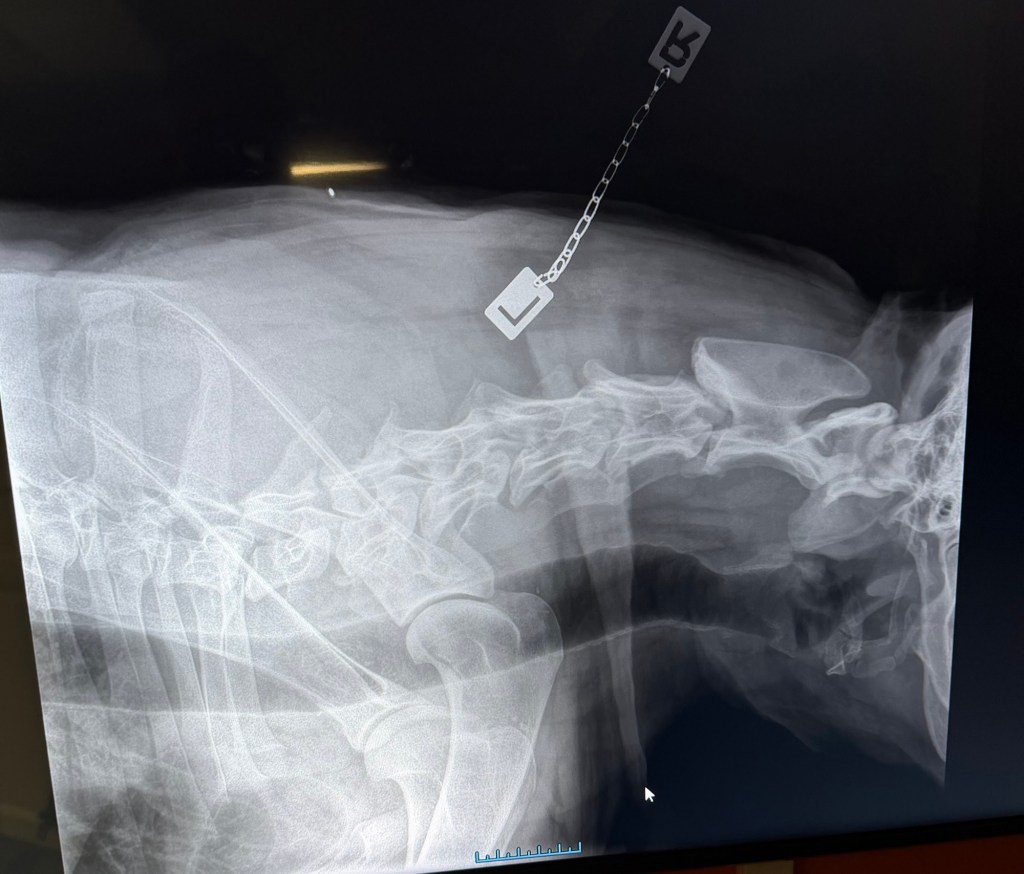

Freki har også vært på røntgen nå i november 2025, i en alder av 3år og 8måneder. Dette grunnet et ønske om å avdekke eventuelle svakheter eller forandringer i skjelett. Freki er en kraftig og stor hund med mye muskler og kraft, så her er det store påkjenninger. Rygg og albuer ble sjekket og resultatene var fantastiske og meget bra! Han har mikroskopiske forandringer i rygg og en flott bakpart med robust lende-rygg. Albuene er som tidligere, uten stor signifikant forandring. En frisk og sunn 4 åring! Freki har et utrolig flott vesen og er en ordentlig glad Bamse-gutt med masse kjærlighet til alle.